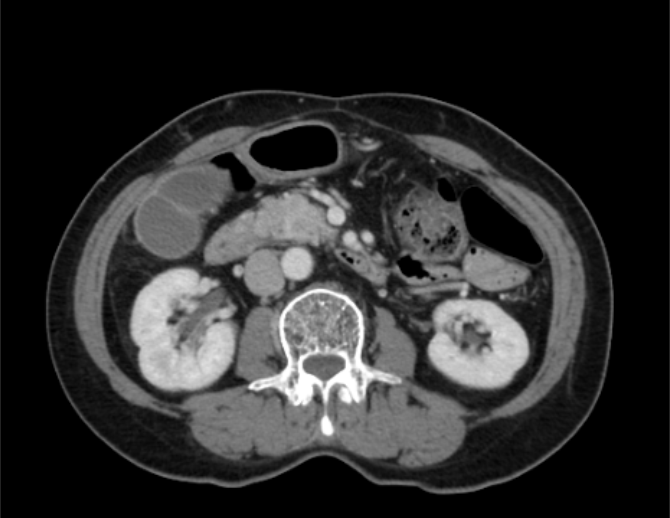

PANCREASaver® 專注於那些容易被忽略的微小病灶

病灶特徵不明顯,肉眼易疲勞漏看

偵測到早期隱形病灶

* 本案例展示 AI 如何在複雜影像中定位高風險區域,提升早期發現率。